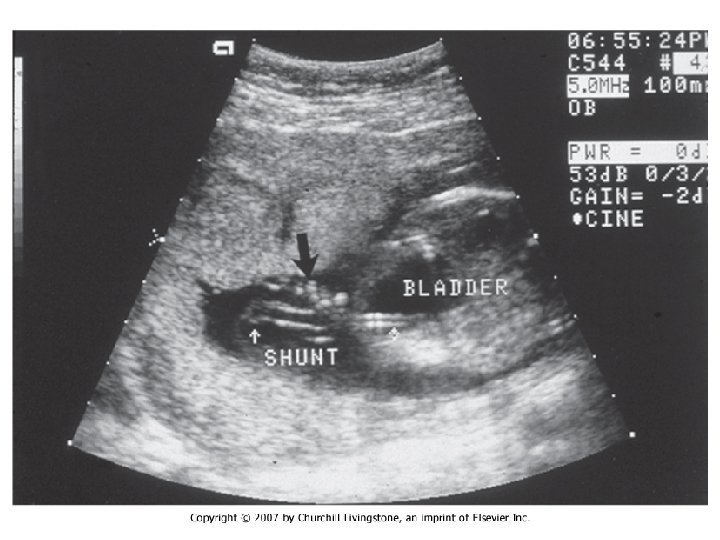

In Utero Fetal Therapy Meningomyelocele

In Utero Fetal Therapy Bladder Outlet Obstruction